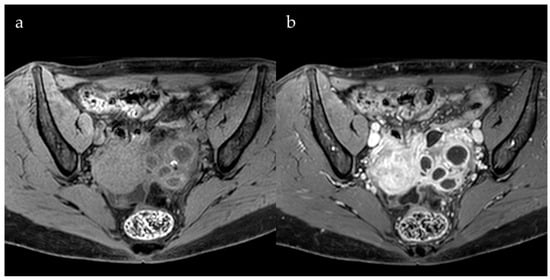

3. Role of Contrast Agents

- Bazot, M.; Gasner, A.; Lafont, C.; Ballester, M.; Daraï, E. Deep pelvic endometriosis: Limited additional diagnostic value of postcontrast in comparison with conventional MR images. Eur. J. Radiol. 2011, 80, e331–e339. [Google Scholar] [CrossRef] [PubMed]

- Onbas, O.; Kantarci, M.; Alper, F.; Kumtepe, Y.; Durur, I.; Ingec, M.; Gursan, N.; Okur, A. Nodular endometriosis: Dynamic MR imaging. Abdom. Imaging 2007, 32, 451–456. [Google Scholar] [CrossRef]